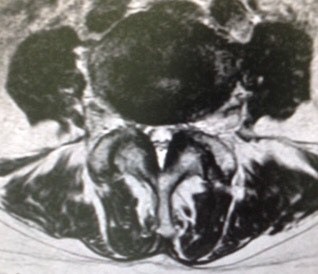

図の左側なんて狭苦しいでしょう‼️コレが脊柱管の『狭窄』と呼ばれる状態ですね。実際のMRIをどうぞ。まずは正常な部位。

次が狭窄部位。一目瞭然でしょうが・・・では、この方にどんな症状が❓

次が狭窄部位。一目瞭然でしょうが・・・では、この方にどんな症状が❓痛み、しびれ、間歇性跛行、膀胱直腸障害・・・など、

ナニモありません‼️